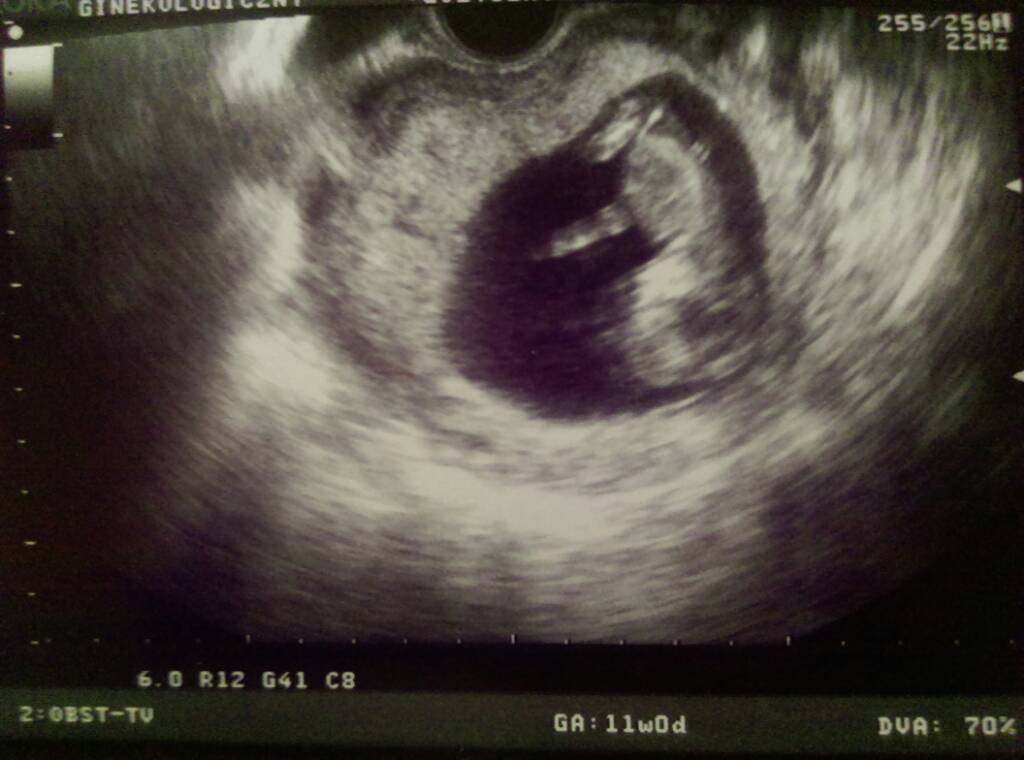

Wczoraj mialam badania prenatalne.

Przeziernosc karkowa wyszla 2,5 przy clr 4.98.

Ten lekarz badal nas bardzo dlugo, maluch nie chcial sie obrocic do pomiarów, musialam ja sie obracac, kaszlec itp.